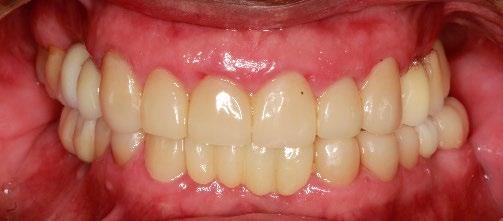

Se presenta un paciente de 18 años de edad que refiere tener hemofilia tipo A, moderado grado V. En los estudios de inicio extraorales, se observa en la Figura 1 el frente, sonrisa y perfil. En la radiografía lateral de inicio (Figura 2) se evidencian el overjet y overbite reducidos, clase I esquelética, hiperdivergencia y biprotrusión dentoalveolar.

En los estudios intraorales, las fotografías iniciales muestran clase I canina y molar bilateral, mordida anterior abierta, apiñamiento leve superior e inferior, y líneas medias dentales

desviadas. En las Figuras 4, 5 y 6 se observa la forma de las arcadas superior e inferior.

El tratamiento concluyó en 2 años y 6 meses, logrando el perfil facial deseado, con clase I esquelética, clase I canina y molar bilaterales, corrección del apiñamiento maxilar y mandibular, líneas medias coincidentes, overjet y overbite adecuados, así como la realización de la genioplastia e implantes en la zona malar. En los

En los estudios finales en las fotografías intraorales (Figura 9) se ve la línea media coincidente, el overjet y el overbite. La alineación y forma de las arcadas superior e inferior, con el